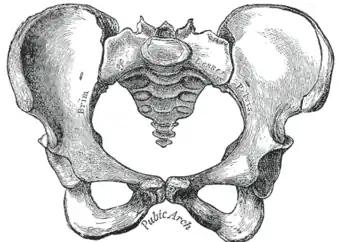

-

Becken -

Zugleich wird unter dem Begriff „Becken“ auch der knöcherne Teil dieses Körperabschnitts verstanden. Das knöcherne Becken besteht aus den beiden Hüftbeinen (Ossa coxae) und dem Kreuzbein (Os sacrum), sie bilden den Beckengürtel oder auch Beckenring (Cingulum membri pelvini). Bei Säugetieren (einschließlich des Menschen) ist das knöcherne Becken mit der Wirbelsäule über das Iliosakralgelenk gelenkig, aber wenig beweglich[1], verbunden. Durch seine Festigkeit und Stabilität gibt der Beckengürtel dem menschlichen Körper einen sicheren Stand und eine aufrechte Haltung. Zudem umgibt es die Beckenhöhle. Bei Tieren sorgt es dafür, dass die Hintergliedmaßen stabil am Rumpf verankert werden und der von ihnen produzierte Vorschub effektiv auf den Körper übertragen wird. Bei Krokodilen unterstützt der Beckengürtel die Lungenventilation.[2]

Beide Hüftbeine sind über das Kreuzbein-Darmbein-Gelenk (Articulatio sacroiliaca) mit dem Kreuzbein verbunden. Dieses Gelenk ist eine Amphiarthrose, also ein straffes Gelenk, das kaum Bewegungen ausführen kann, aber für die Federung der Wirbelsäule von großer Wichtigkeit ist. An der Vorderseite haben die beiden Hüftbeine eine knorpelige Verbindung über die Schambeinfuge (Symphysis pubica). Bei Tieren liegt die Verbindung zwischen beiden Hüftknochen an der Unterseite und schließt Scham- und Sitzbein ein (Symphysis pelvica).

Alle drei Hüftknochen treffen in der Hüftgelenkpfanne (Acetabulum) zusammen, welche mit dem Kopf des Oberschenkelknochens das Hüftgelenk bildet.